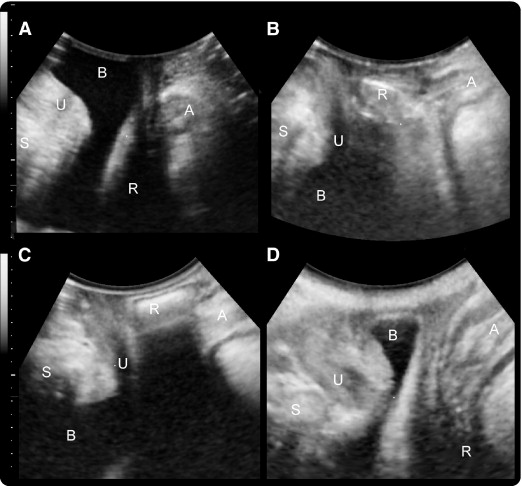

A pelvic ultrasound is a noninvasive diagnostic exam that produces images that are used to assess organs and structures within the female pelvis. A pelvic ultrasound allows quick visualization of the female pelvic organs and structures including the uterus, cervix, vagina, fallopian tubes and ovaries.

Pelvic ultrasound may be performed using one or both of 2 methods:

Transabdominal (through the abdomen). A transducer is placed on the abdomen using the conductive gel

Transvaginal (through the vagina).

A long, thin transducer is covered with the conducting gel and a plastic/latex sheath and is inserted into the vagina

The type of ultrasound procedure performed depends on the reason for the ultrasound. Only one method may be used, or both methods may be needed to provide the information needed for diagnosis or treatment.

There are two ways to perform an ultrasound — abdominally and transvaginally.

A transvaginal ultrasound is an internal scan of the female reproductive organs. It involves inserting a small ultrasound probe, called a transducer, into the vagina to produce incredibly detailed images of the organs in the pelvic region.

Doctors may use the term “pelvic ultrasound” to describe both a transvaginal and a transabdominal ultrasound. During a transabdominal ultrasound, the person performing the scan uses the probe outside the abdomen.

By comparison, a transvaginal ultrasound can provide more close-up images of the internal organs than an external pelvic ultrasound.